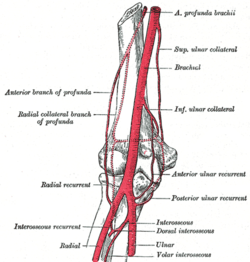

Blood supply

The arteries supplying the joint are derived from an extensive circulatory anastomosis between the brachial artery and its terminal branches. The superior and inferior ulnar collateral branches of the brachial artery and the radial and middle collateral branches of the profunda brachii artery descend from above to reconnect on the joint capsule, where they also connect with the anterior and posterior ulnar recurrent branches of the ulnar artery; the radial recurrent branch of the radial artery; and the interosseous recurrent branch of the common interosseous artery.[12]

The blood is brought back by vessels from the radial, ulnar, and brachial veins. There are two sets of lymphatic nodes at the elbow, normally located above the medial epicondyle — the deep and superficial cubital nodes (also called epitrochlear nodes). The lymphatic drainage at the elbow is through the deep nodes at the bifurcation of the brachial artery, the superficial nodes drain the forearm and the ulnar side of the hand. The efferent lymph vessels from the elbow proceed to the lateral group of axillary lymph nodes. [12] [13]